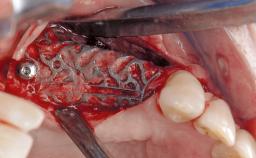

In this case, Mario Roccuzzo utilizes surgical bone regeneration treatment around implant 46 using a bone graft substitute and a connective tissue graft to resolve peri-implant inflammation, reduce the probing depths, and prevent further progression of disease.

A 58-year-old-male patient was referred in February 2007 for implant placement in the right mandibular molar area. Two tissue level implants were inserted at sites 44 and 46, respectively, to support a three-unit fixed dental prosthesis (FDP).